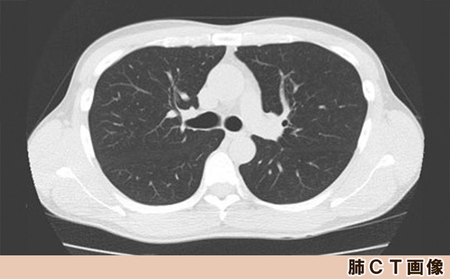

・肺CT検査

◆肺CT検査

CTを使用した詳しいX線検査です。通常の胸部X線検査だけでは早期の小さな肺がんの発見は困難です。CTによって早期の肺がん発見を目指します。